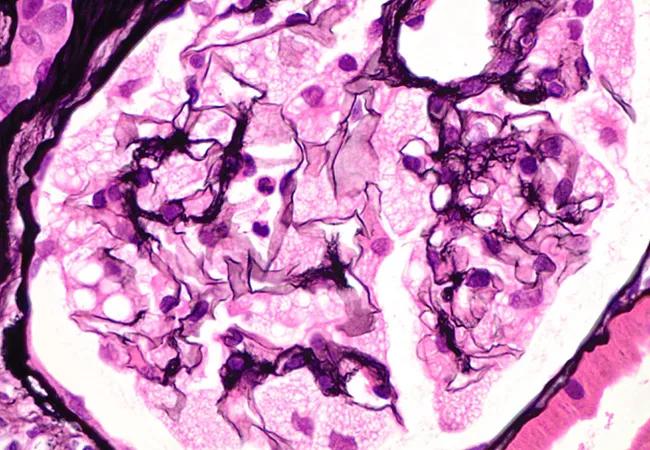

Featured image: Renal biopsy from a patient with Fabry disease, confirmed after renal biopsy with genetic testing. The biopsy showed glomeruli with “foamy” podocytes due to the accumulation of lipid material within the cytoplasm. Jones methenamine silver x600 magnification. Copyright © 2023 Sawaf et al. This work is published and licensed by Dove Medical Press Limited. The image and its description were reprinted with permission under the Creative Commons Attribution – Non Commercial (unported, v3.0) License (http://creativecommons.org/licenses/by-nc/3.0/)